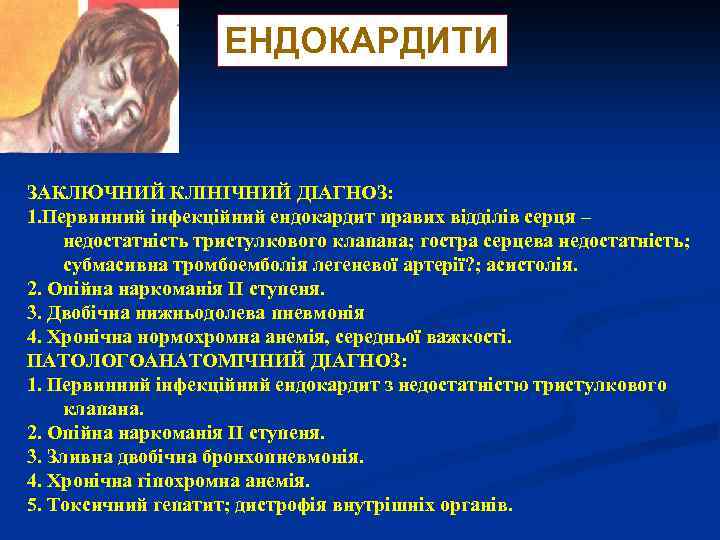

ЕНДОКАРДИТИ ЗАКЛЮЧНИЙ КЛІНІЧНИЙ ДІАГНОЗ: 1. Первинний інфекційний ендокардит правих відділів серця – недостатність тристулкового клапана; гостра серцева недостатність; субмасивна тромбоемболія легеневої артерії? ; асистолія. 2. Опійна наркоманія ІІ ступеня. 3. Двобічна нижньодолева пневмонія 4. Хронічна нормохромна анемія, середньої важкості. ПАТОЛОГОАНАТОМІЧНИЙ ДІАГНОЗ: 1. Первинний інфекційний ендокардит з недостатністю тристулкового клапана. 2. Опійна наркоманія ІІ ступеня. 3. Зливна двобічна бронхопневмонія. 4. Хронічна гіпохромна анемія. 5. Токсичний гепатит; дистрофія внутрішніх органів.